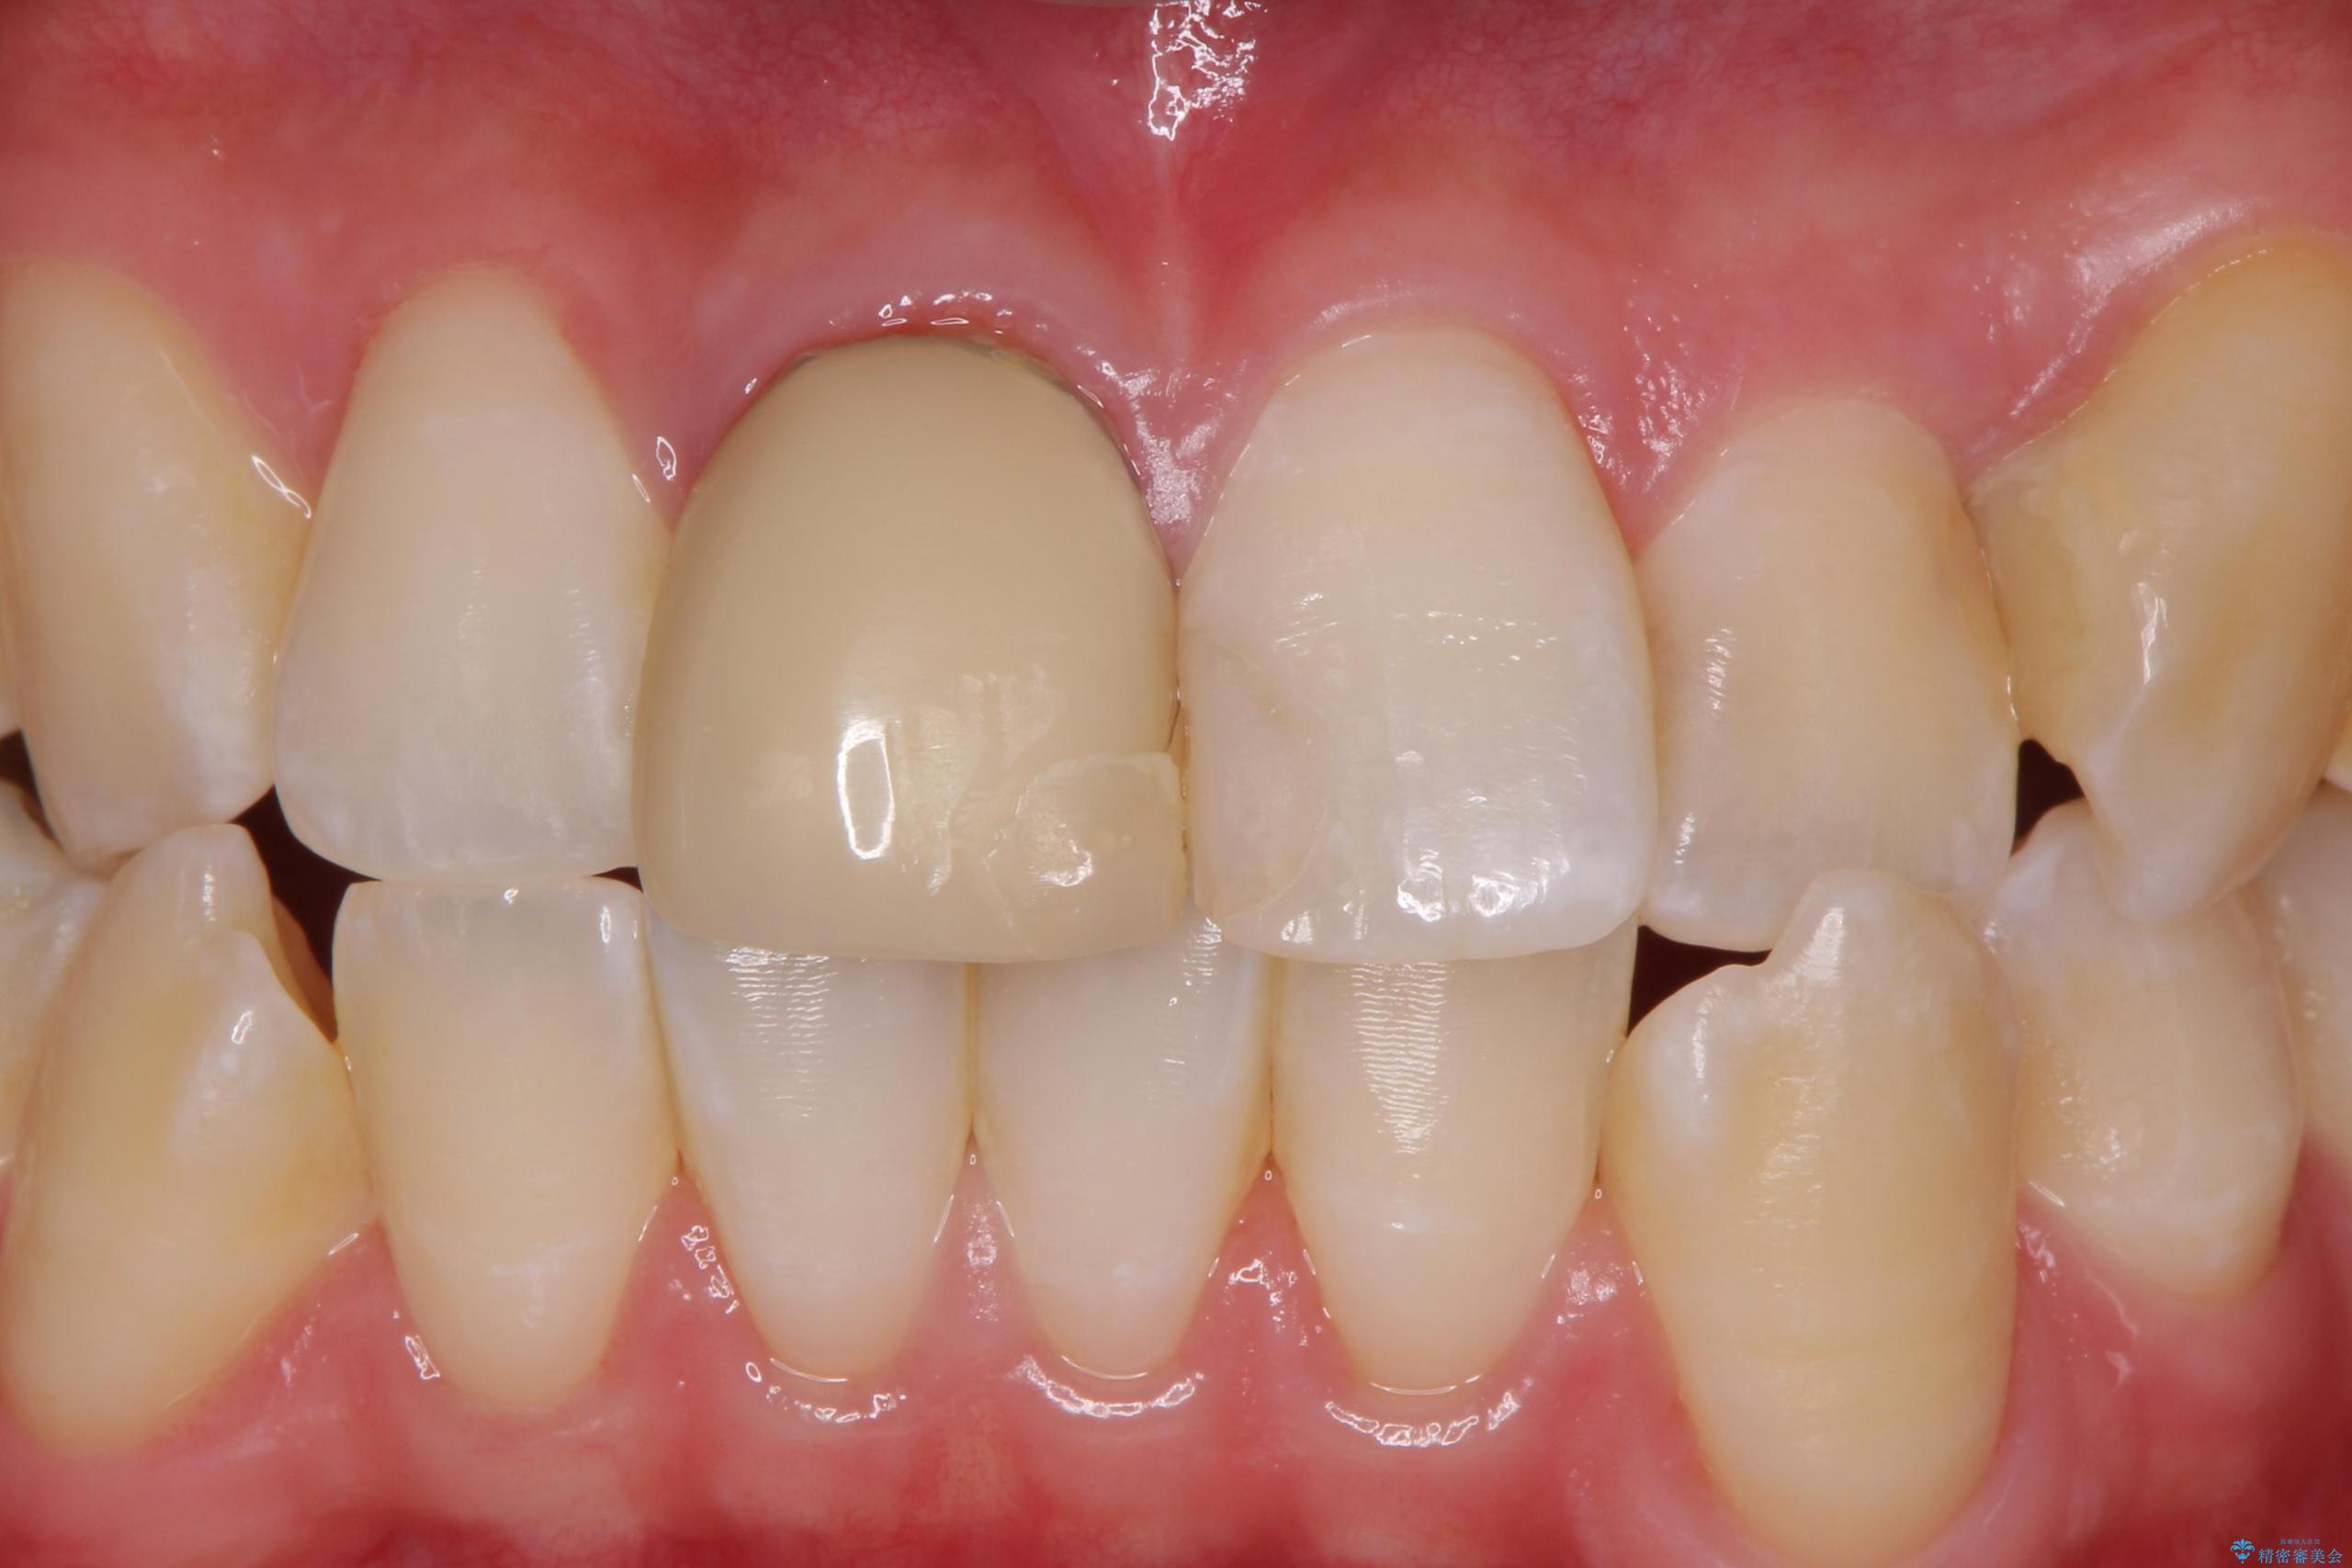

- 右上1: 仮歯/11,000円、ジルコニアクラウン(スタンダード)/121,000円 合計132,000円(税込)費用は治療当時の料金となります

色・形ともに改善され、大変喜んでいただけました。